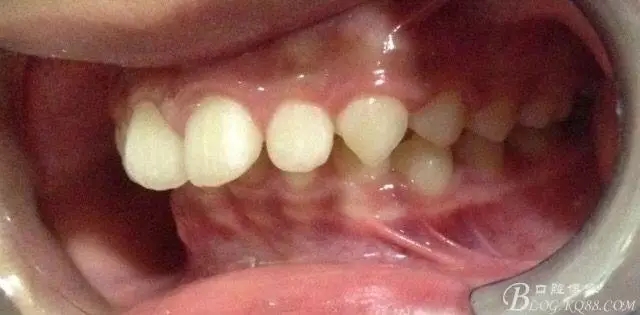

看看口內(nèi)照吧!真象“大暴牙”v假象“大暴牙”

三度深覆合,三度深覆蓋,尖牙,磨牙均二類關系!